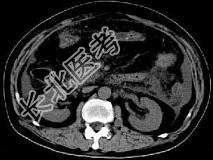

- 单项选择题根据所提供的图像,最可能的诊断是 ( )

A、胰腺癌

B、急性胰腺炎

C、慢性胰腺炎

D、正常胰腺

E、以上都不是